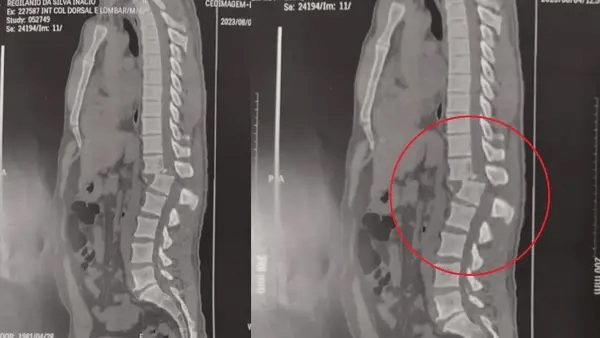

A confiança da família na recuperação se deve ao sucesso do procedimento cirúrgico, que já deu a Regilânio uma vitória: nesta terça-feira ele conseguiu sentar pela primeira vez. Duas imagens de raio-x mostram o antes e depois da cirurgia. A primeira, feita antes do procedimento, revela a coluna vertebral do paciente fraturada entre as vértebras T12 (fim da parte torácica) e L1 (início da parte lombar). Já na segunda imagem é possível verificar que a região voltou a ficar alinhada.